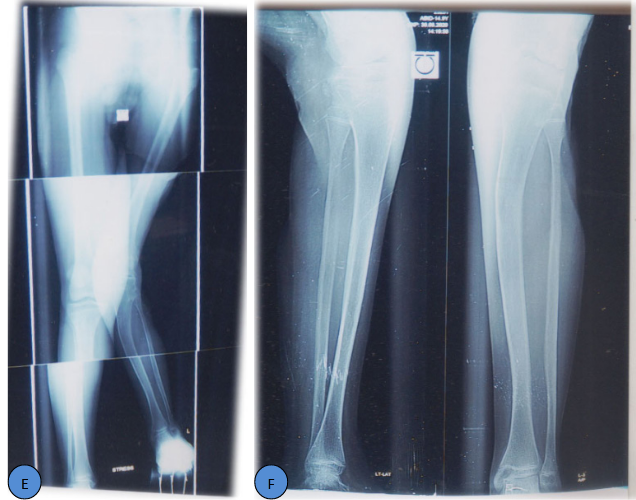

A 14 years old boy sustained motor vehicle injury in the left inferior extremity at the age of 8. He was treated at Combined Military Hospital, Dhaka at that time because father is an Army personnel. Now, he was referred to Bari-Ilizarov Orthopaedic Centre for further management, that is for correction of deformity and L. L. D. Plain X-ray and clinical ndings showed his left lower extremity with distal femur valgus deformity, proximal tibia valgus and procurvatum deformity. He was complaining left knee pain and his gait was awkward. His father was anxious regarding his deformity correction and lengthening of left lower limb.1–5

Figure 1 A-J 14 years old boy, Post Traumatic Genu Valgum with Valgus Deformity of left Lower Femur and Upper Tibia Valgus and Procurvatum Deformity with 10cm L. L. D and Puckering of Skin around Knee with Bad Scar.